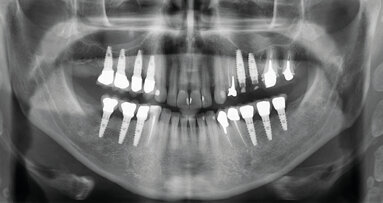

Examen clinique et radiologique L’examen clinique et radiographique met en évidence la possibilité de poser un implant (Figs. 1 et 2).

Fig. 1 : Radio panoramique, on visualise bien le secteur édenté en 46.

À l’issue de l’intervention, vérification de la correspondance entre la planification et la chirurgie avec une rétroalvéolaire (Figs. 11 et 12).

Fig. 13 : Radio panoramique de contrôle postopératoire.